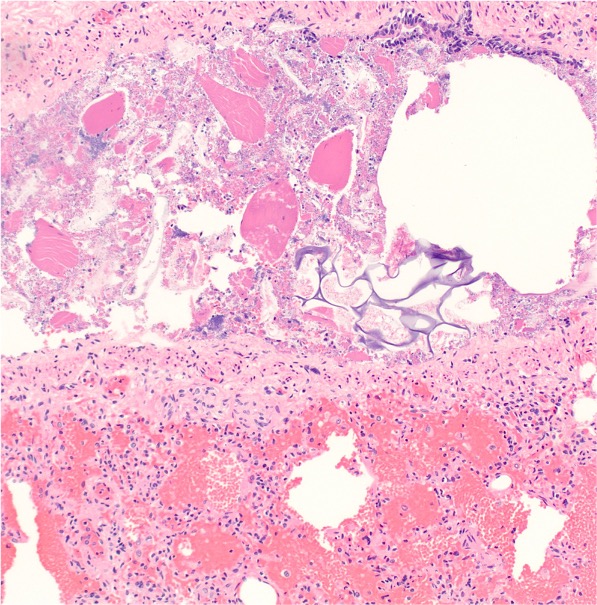

Based on the microscopic images (H&E - 100X), which relevant information has likely been omitted in the case presentation?

A cardiac catheterization procedure was performed with detection of pulmonary arterial hypertension